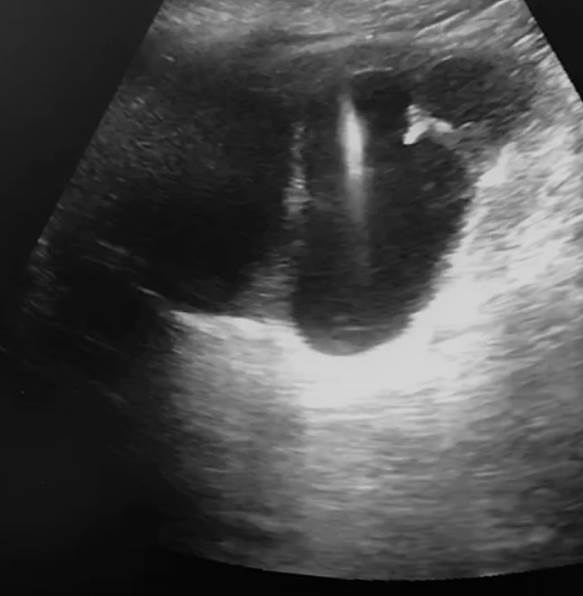

Posterior a la colocación de campos, vestir equipo y transductor de ultrasonido. En este caso se utilizó un ultrasonido marca Vinno E10 versión SW 1.8.0.191 (Sistema OS image: 1.3.41.3), utilizando un transductor doppler curvo de 3.5 MHz, se visualiza el parénquima renal, sistemas colectores, cálculos y órganos adyacentes.

a) Como pauta general, la profundidad de la ecografía se establece en el rango de 8 a 12 cm (esto determina la profundidad a la cual debe introducirse la aguja de Shiva), sin embargo, a pesar de esta pauta, es importante medir la distancia de piel-cáliz previo a la punción y con esto saber hasta que profundidad es necesario introducir la aguda de Shiva (Figura 2 y Figura 3). Se mide la distancia de la piel al colector y se suman 2 a 3 cm (profundidad inferida con la presión que se realiza al momento de colocar el transductor para localizar al riñón, con esta medición logramos concordar con la pauta general de la profundidad de 8 a 12 cm para la punción.

b) Se coloca el transductor a nivel renal obteniendo una imagen de los cálices renales y se selecciona al más adecuado (aquel que permita, de acuerdo a su angulación, la entrada directa a la mayor cantidad de lito para trabajar) para realizar punción con aguja de Shiva 18 gauge 20 cm (si los cálices son difíciles de localizar, se puede realizar inyección retrógrada de forma suave y pasiva de solución salina a través del open-end), la aguja se coloca en el eje longitudinal (adelante o atrás del transductor), de manera que se desplace en paralelo al eje largo del transductor, con el fin de seguir el trayecto de la aguja hasta la profundidad del cáliz renal seleccionado. La punción se realiza por el cirujano. (Figura 4)